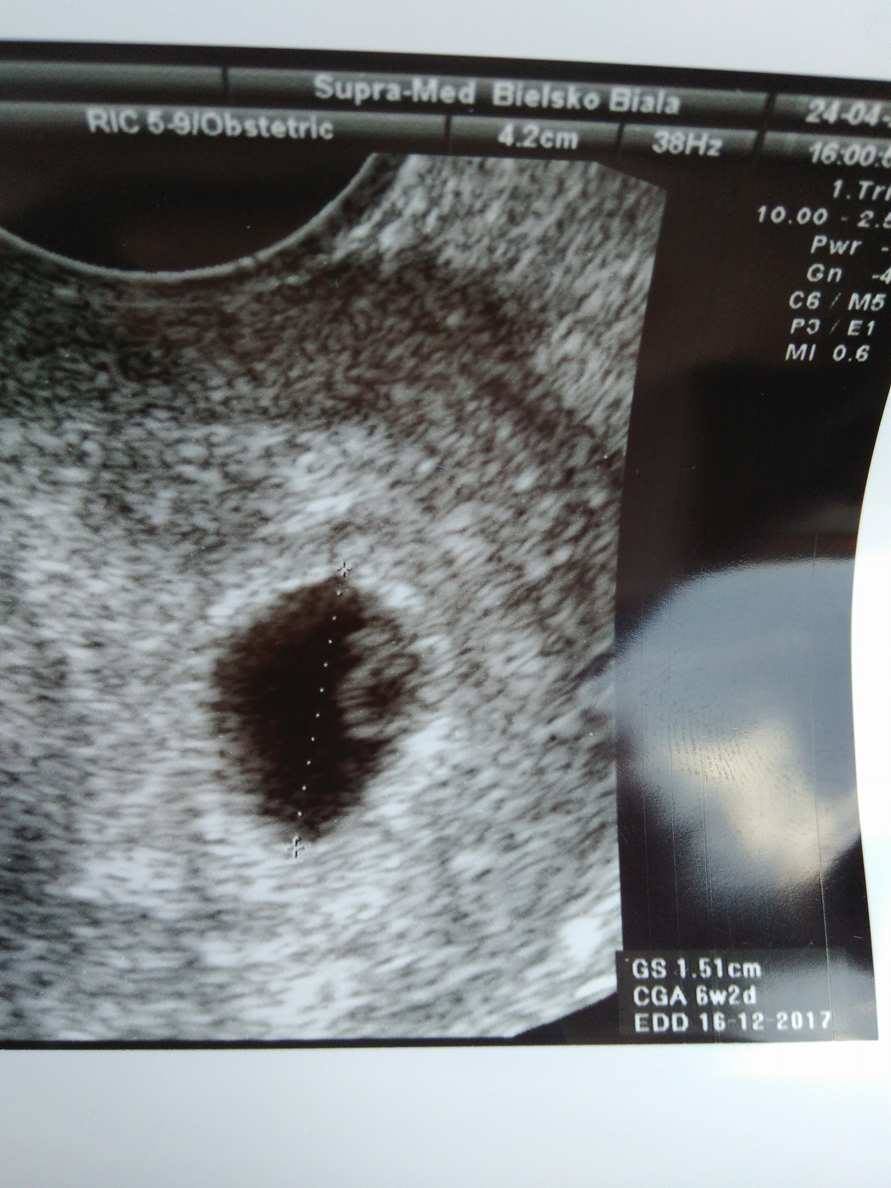

...........:::::::6tydz i 6dni:::::::::..........